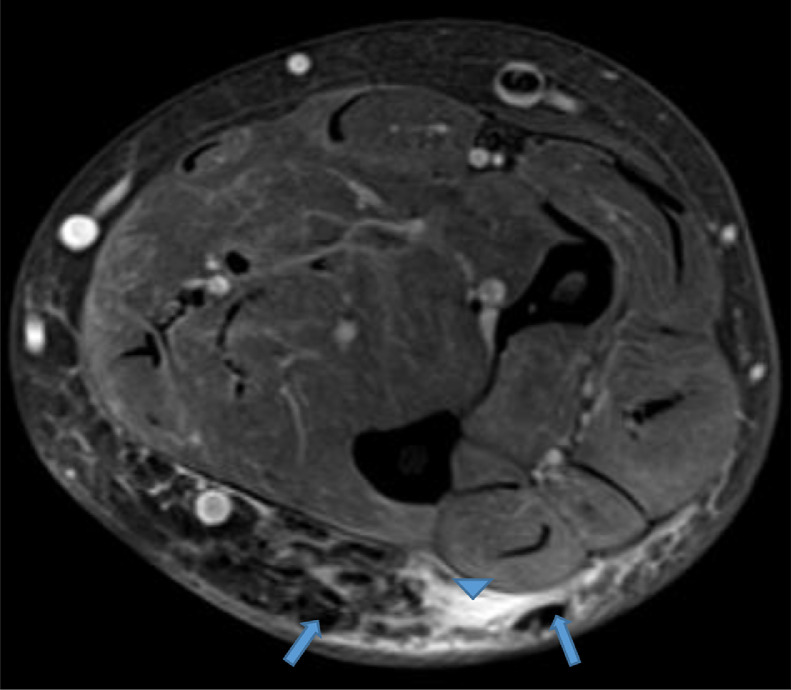

Fig. 2.

Axial proton density (PD) fat saturation image reveals low signal intensity foci (blue arrows) surrounded by high signal intensity fluid infiltrating the subcutaneous fat (blue arrowhead). Color version available online